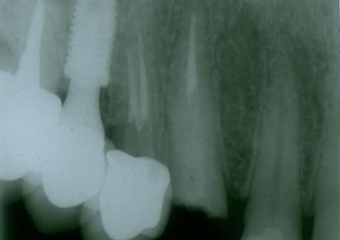

Rx Periapical Pré-cirurgico 03-10-16 - Clínica Cliniface

Rx Periapical Pré-cirurgico 03-10-16